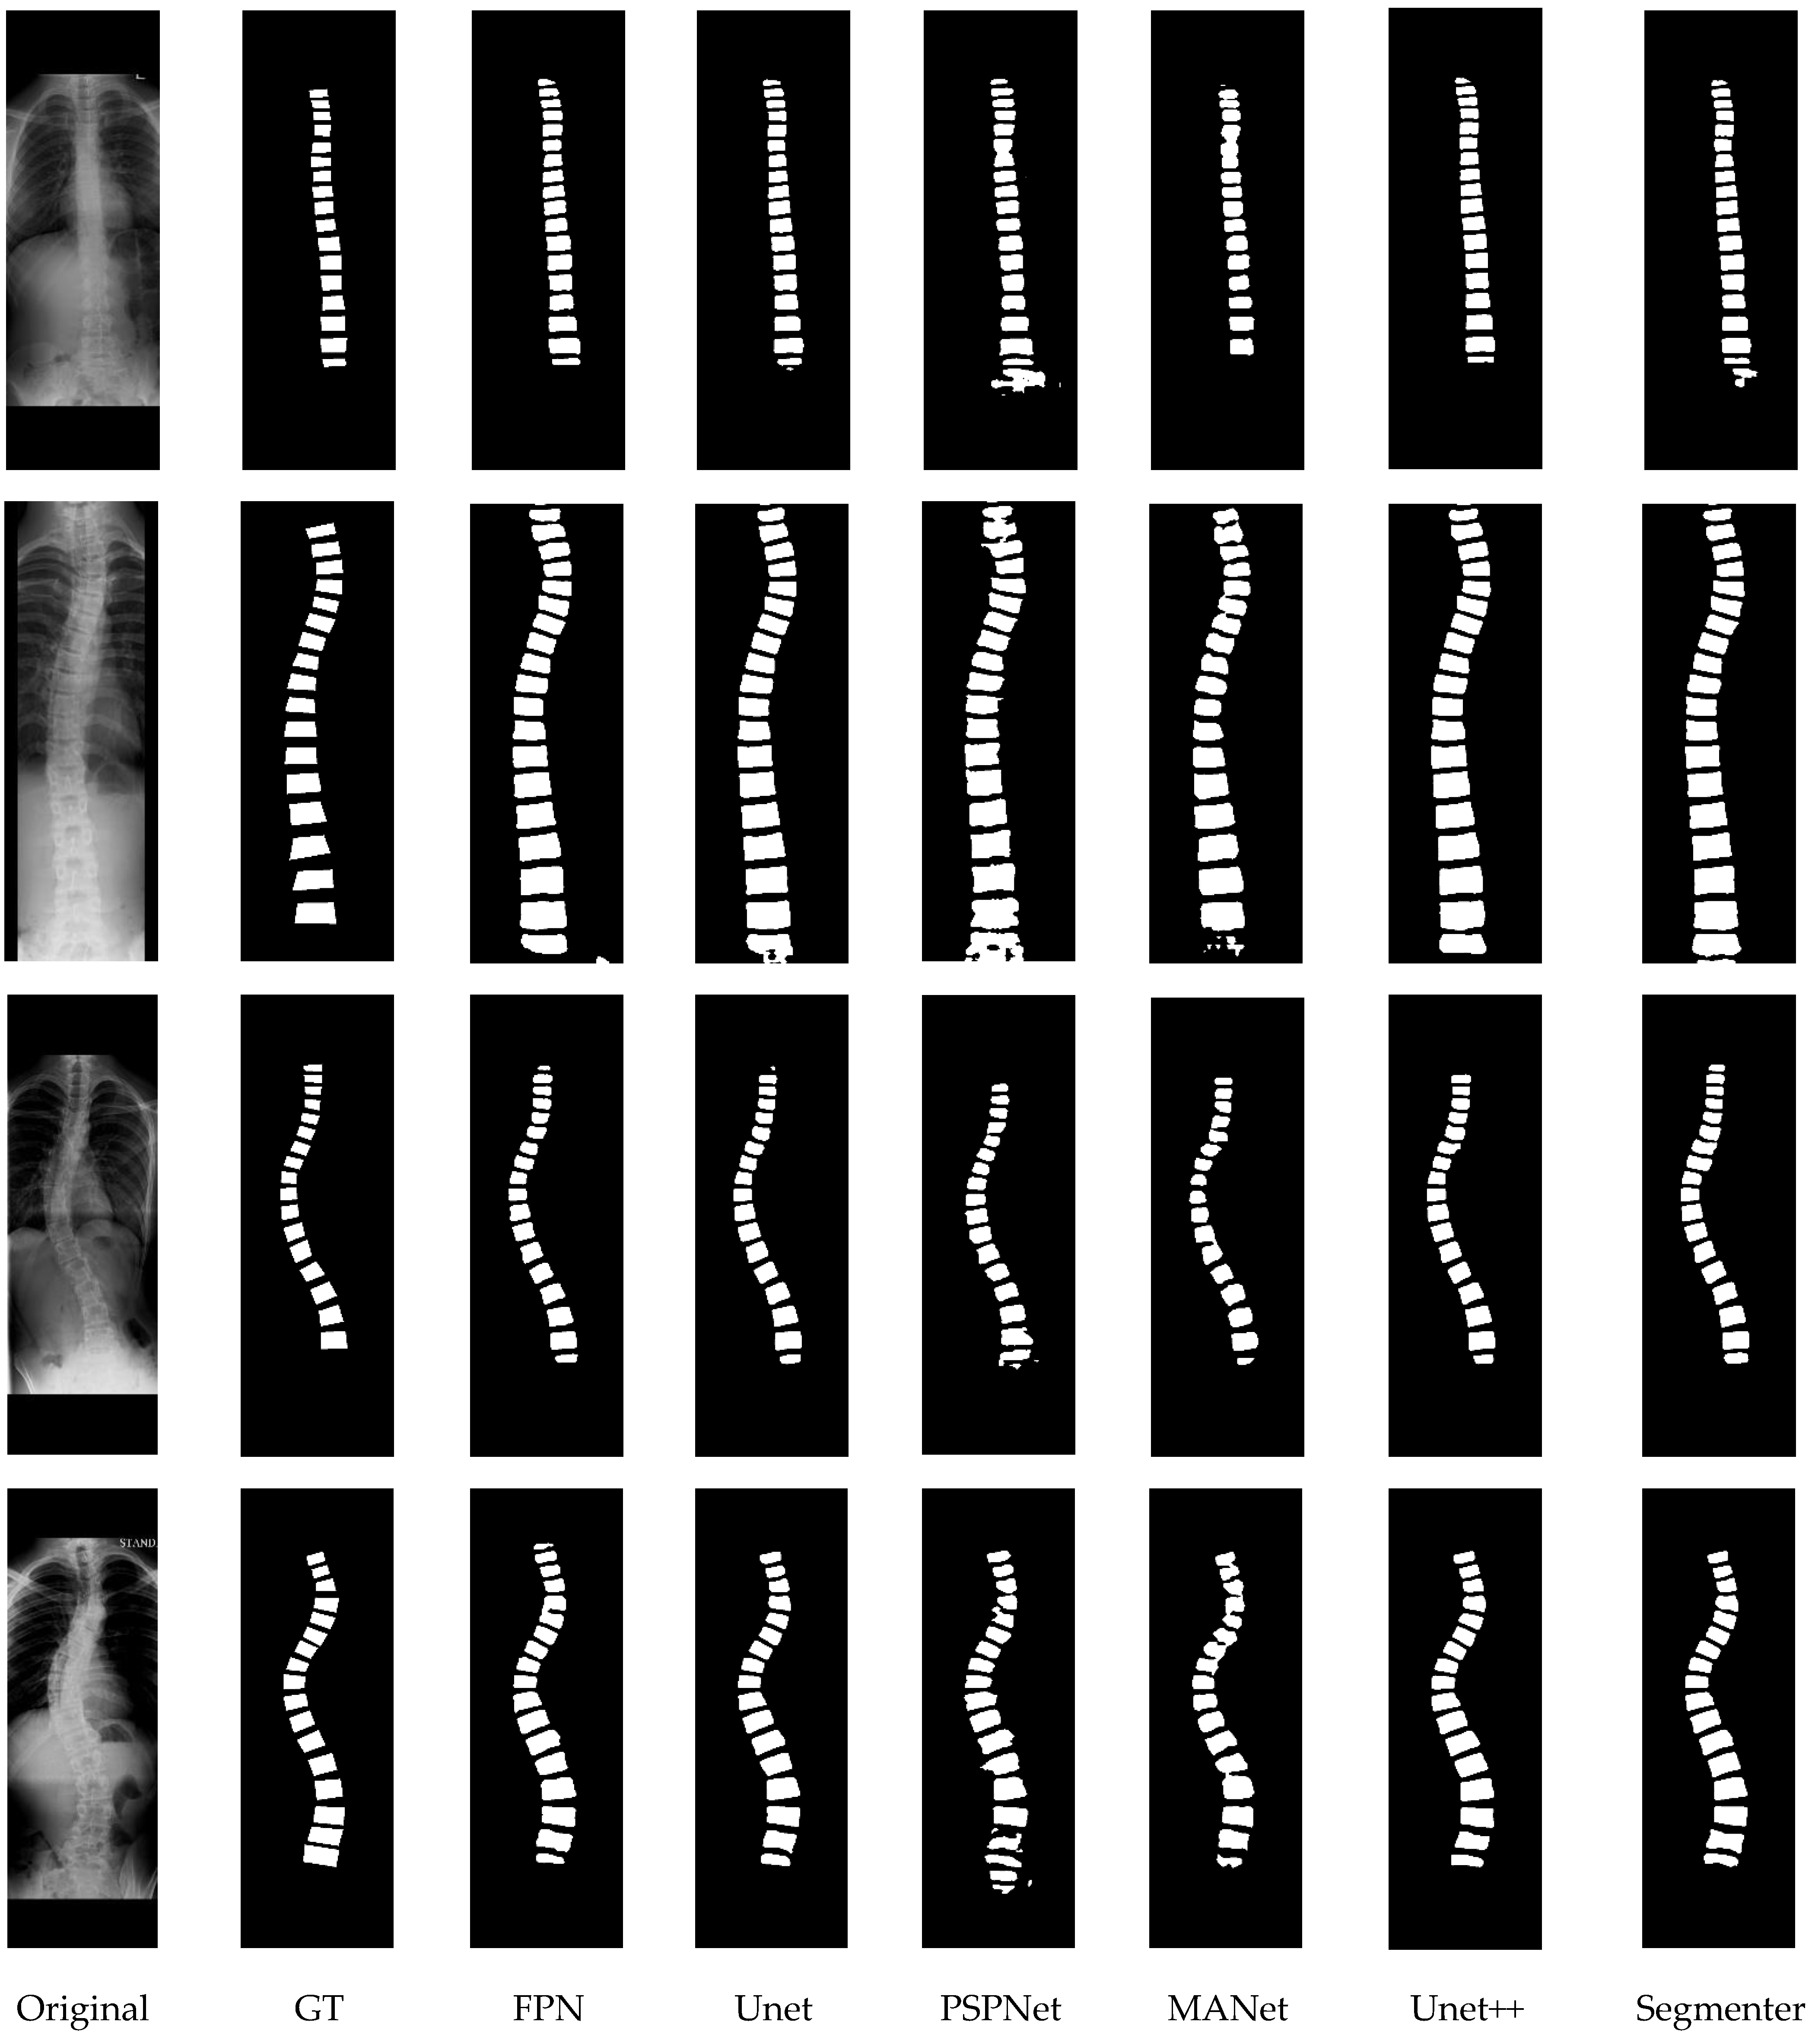

The quantitative experimental results of the compared methods are presented in Table 3, where ⊗ denotes that post-processing was not used for the segmentation results; √ denotes that post-processing was used; and + indicates the increase with the post processing used. To intuitively present the visual comparison, the segmentation effects of the different methods are shown in Figure 14, and some examples that illustrate the effects of post-processing are presented in Figure 15.

Figure 14.

The visual comparison of different segmentation networks. GT: ground truth.

From the above results, the following conclusions can be drawn.

First, as shown in Table 3, the Segmenter achieved the best results with accuracy (0.946), sensitivity (0.915), specificity (0.997), dice (0.915), and MIoU (0.848), while Unet++ achieved the second-best results with accuracy (0.940), sensitivity (0.743), specificity (0.983), dice (0.805), and MIoU (0.679). In general, the accuracy and specificity are relatively superior among these methods, but the sensitivity, dice, and MIoU could be improved. This illustrates that the segmentation network approach is limited in terms of dealing with the details of the segmented vertebrae. More intuitive examples can be found in Figure 14.

Second, by observing the visual comparison in Figure 14, various errors such speckles, adhesions, and redundances exist in the segmentation results for different methods. For example, PSPNet has more speckle errors, and MANet has more adhesion errors. However, Unet++ achieved the best subjective results, which are reflected in the clearer segmentation contour and less adhesion errors. Segmenter has more speckles and adhesions in the subjective presentation than Unet++, even though Segmenter achieves high quantitative evaluation values. This greatly affects the Lenke classification performance of scoliosis, which partly why we use Unet++ as the recommended segmentation network.

Third, by observing the results in Table 3 on whether post-processing was used, we note that the post-processing operation improved all methods under all indicators. This demonstrates that post-processing can effectively improve segmentation. Moreover, these improvements on quantitative segmentation indicators are not significant, as post-processing is primarily designed for subjective adhesions and speckles. From the visual comparison in Figure 15, each method can successfully remove some subjective segmentation errors, such as adhesions, speckles, and holes, which significantly contributes to the Lenke classification of scoliosis. In addition, it is worth noting that the post-processing strategy improved Unet++ and Unet more significantly than the other approaches from both objective indicator and subjective observation. This also causes Unet++ to be more advantageous in the Lenke classification of scoliosis. In the next section, we conduct more experiments to verify the performance of the segmentation networks involved in the proposed Lenke classification framework.

In summary, the Unet++ and Segmenter models achieved relatively superior segmentation results with post-processing. In addition, in the next sections, we further test the performance of these segmentation models that are incorporated into the proposed Lenke classification framework of scoliosis.